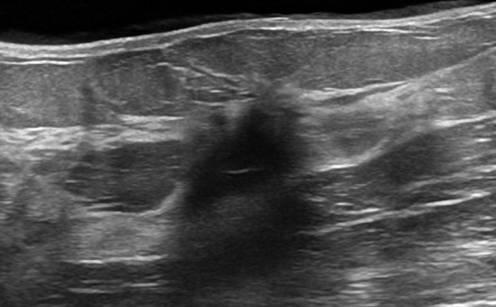

Ung thư vú

Ung thư vú - Ảnh 3

» Thông tin: Nữ giới – 50 tuổi.

» Lâm sàng: Khối tuyến vú.